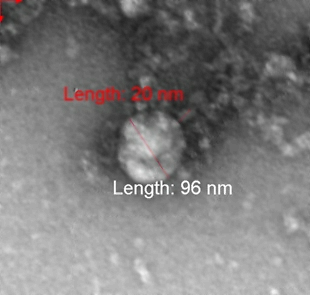

Информация Федеральной службы по надзору в сфере защиты прав потребителей и благополучия человека от 25 января 2021 г. "Учеными Роспотребнадзора получено первое изображение британского штамма нового коронавируса"

ФБУН ГНЦ "Вектор" Роспотребнадзора впервые в мире сфотографировал британский штамм коронавируса, выделенный от пациента в декабре 2020 года.

Фотография вируса под микроскопом получена в рамках продолжающегося изучения свойств данного варианта нового коронавируса, включая его структурные особенности и проявления в клеточных культурах и экспериментальных моделях с использованием лабораторных животных.

ФБУН ГНЦ "Вектор" Роспотребнадзора впервые в мире сфотографировал британский штамм коронавируса, выделенный от пациента в декабре 2020 г.